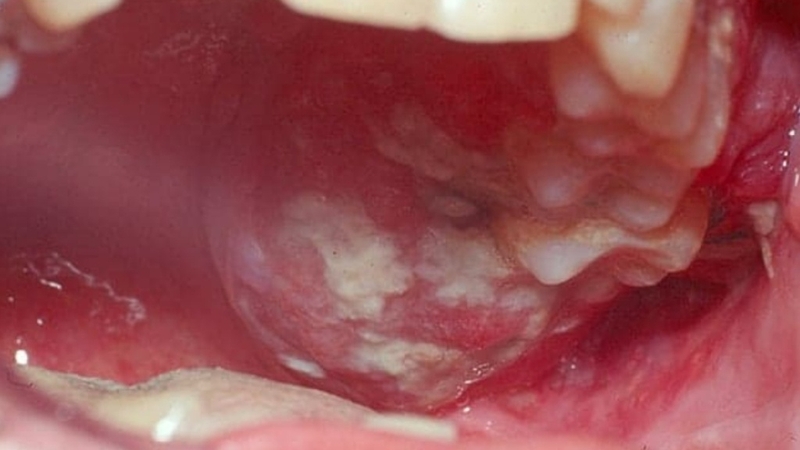

Ung thư khoang miệng giai đoạn đầu thường biểu hiện qua những tổn thương nhỏ mà ban đầu dễ bị nhầm lẫn với viêm loét thông thường. Tuy nhiên, điểm khác biệt là những tổn thương này không tự lành sau 2 tuần và có xu hướng lan rộng. Một số hình ảnh ung thư khoang miệng giai đoạn đầu phổ biến bao gồm:

Mảng trắng (bạch sản) hoặc mảng đỏ (hồng sản): Các mảng này không bị tróc ra khi chà xát.

Sưng cục hoặc nổi hạch trong miệng: Một số u cục xuất hiện ở lưỡi hoặc sàn miệng và không gây đau ban đầu.